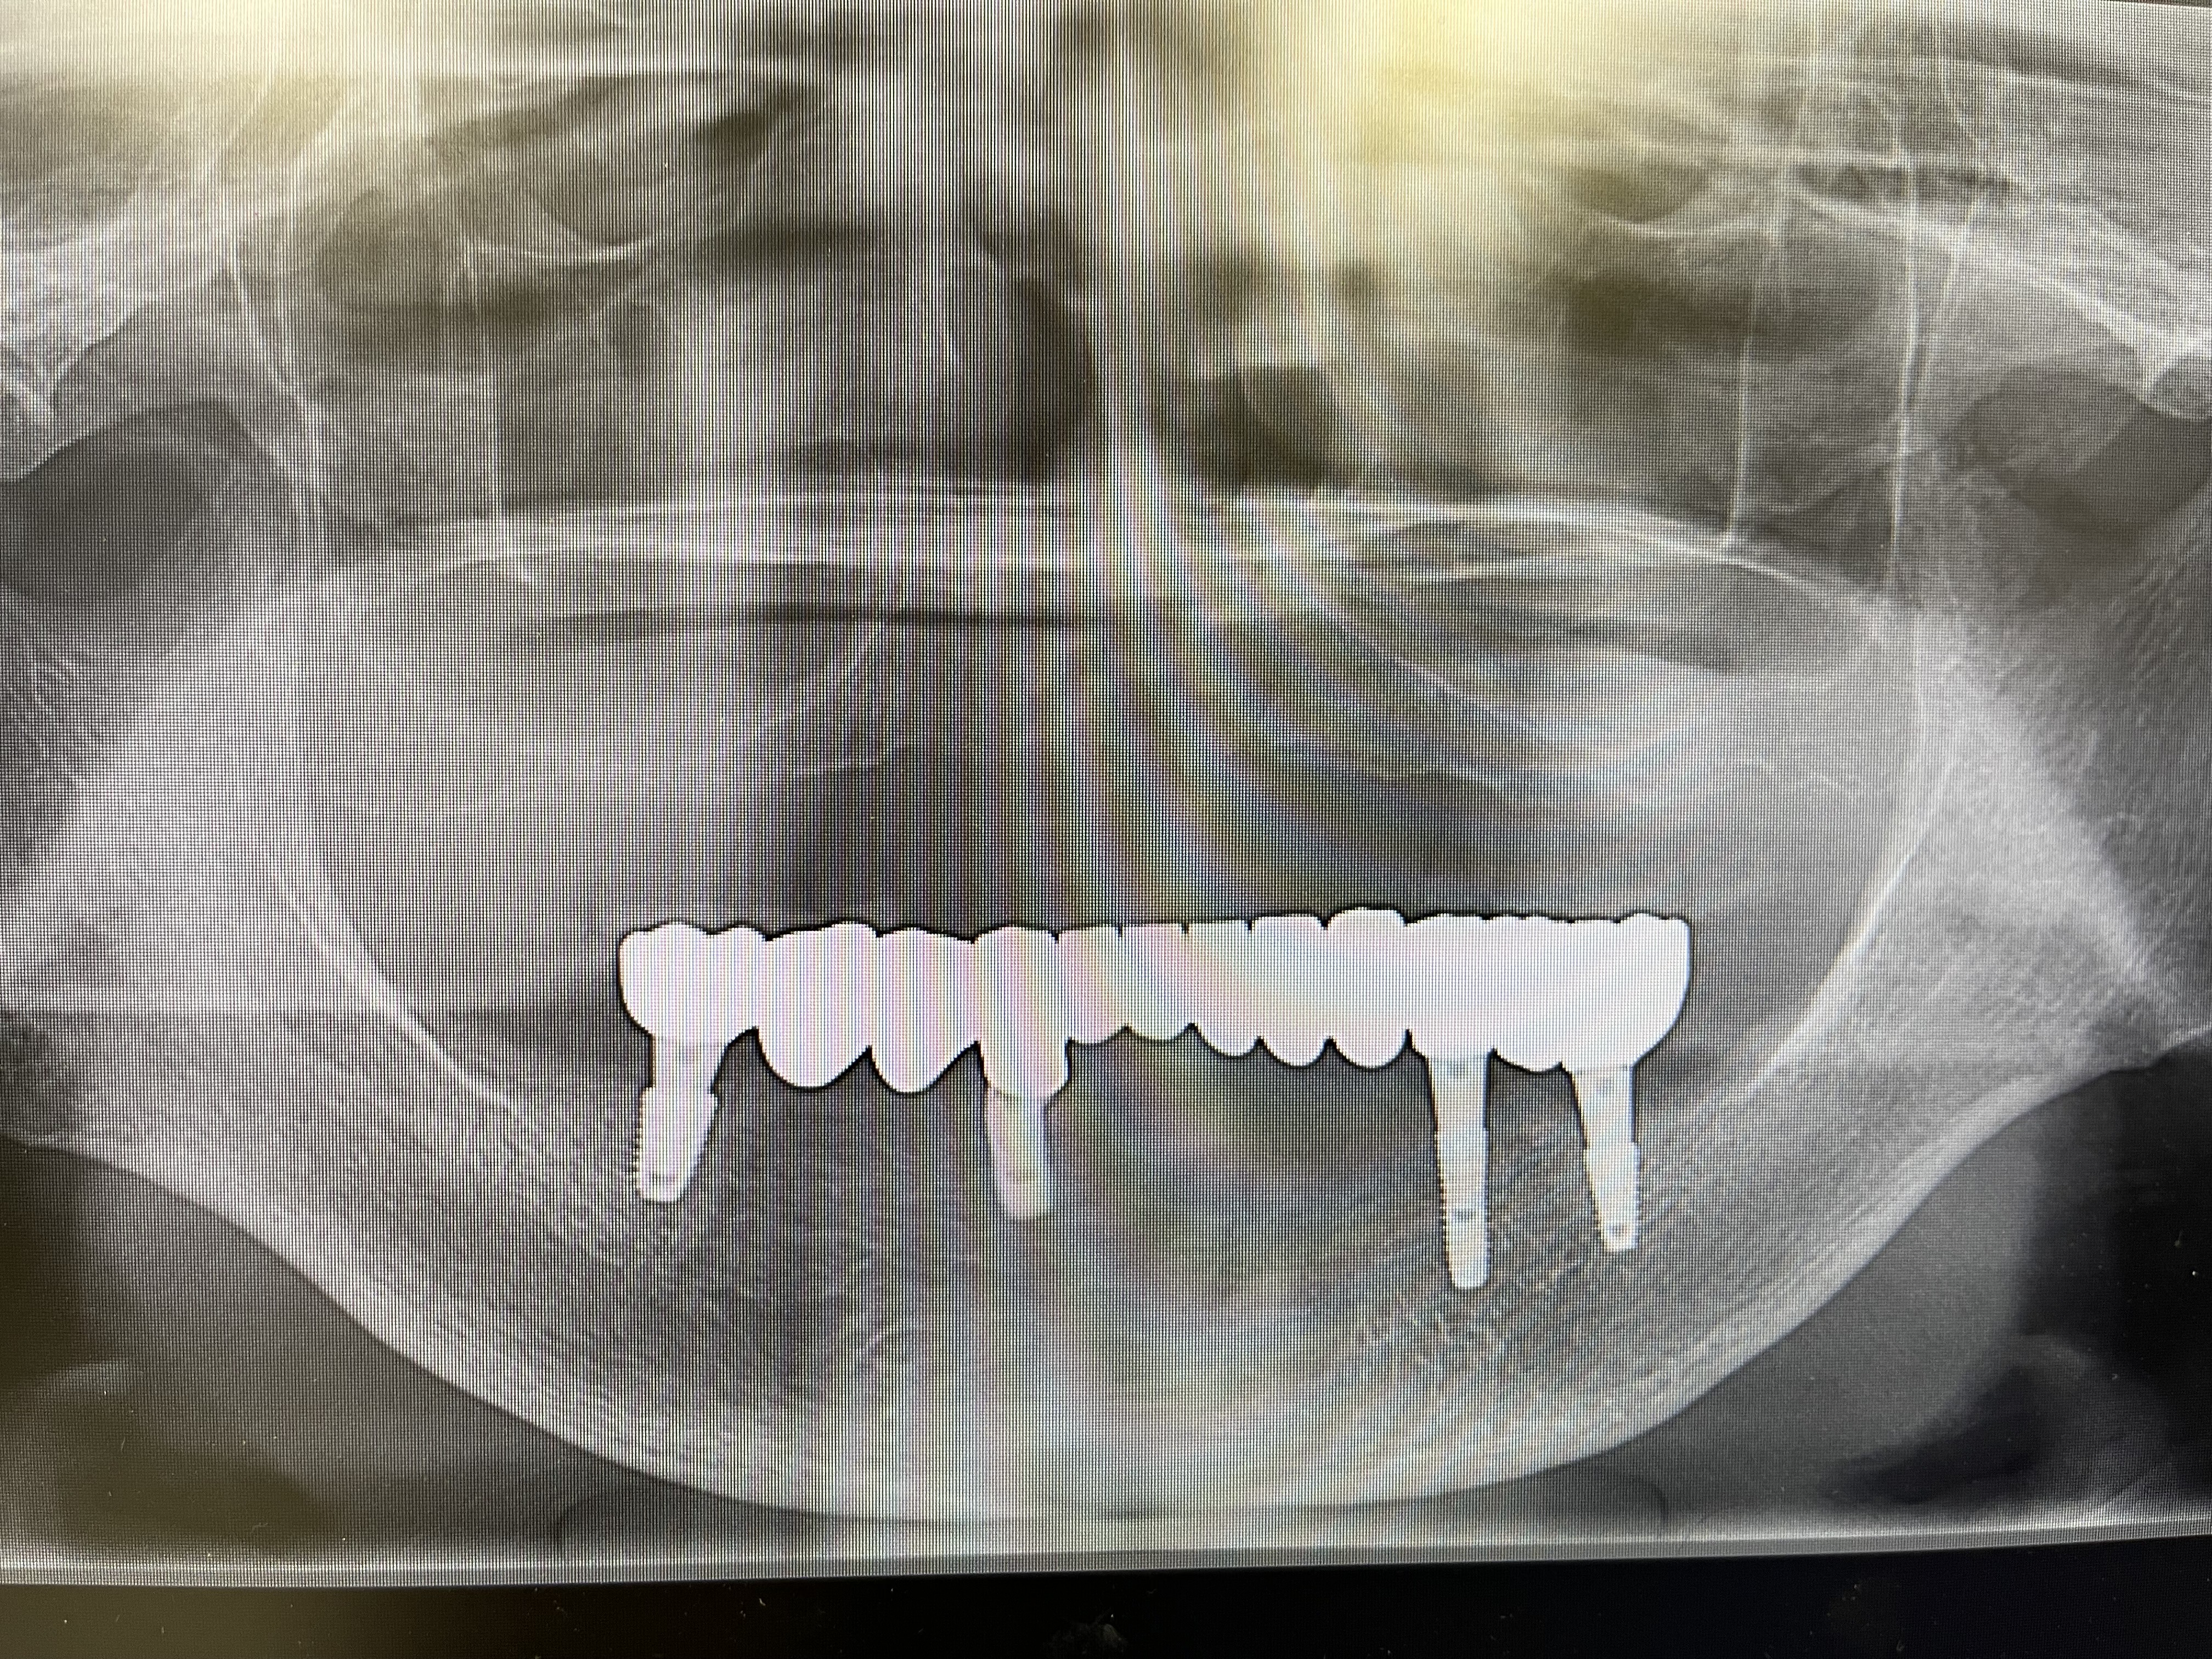

Title ” 総義歯の患者様のインプラント症例”

2024年暮れ、義歯(入れ歯)の痛みで

食事ができない患者様(75歳)が来院されました。

診察をしたところ、下顎の骨の痩せ方が著しく

義歯(入れ歯)が安定しにくいため

固定式のインプラントを提案しました。

固定式のインプラントをすることで、

上顎も外れない安定した総義歯になるということです。

下顎インプラントを4本埋入した状態

インプラントが4本埋入した下顎模型

下顎インプラント模型に仮歯が入っている状態

上部構造が入っている状態(下顎パノラマ写真)

下顎口腔内に最終補綴物(被せ物)が入っている状態

上顎総義歯&下顎インプラントブリッジが入っている状態(口腔内写真)

以上が簡潔にまとめた

総義歯&インプラントブリッジの概要資料となります。

この方法で治療計画を進めたことで、

義歯の装着時に伴う痛みが解消され

なんでも食べることが出来る状態になりました。